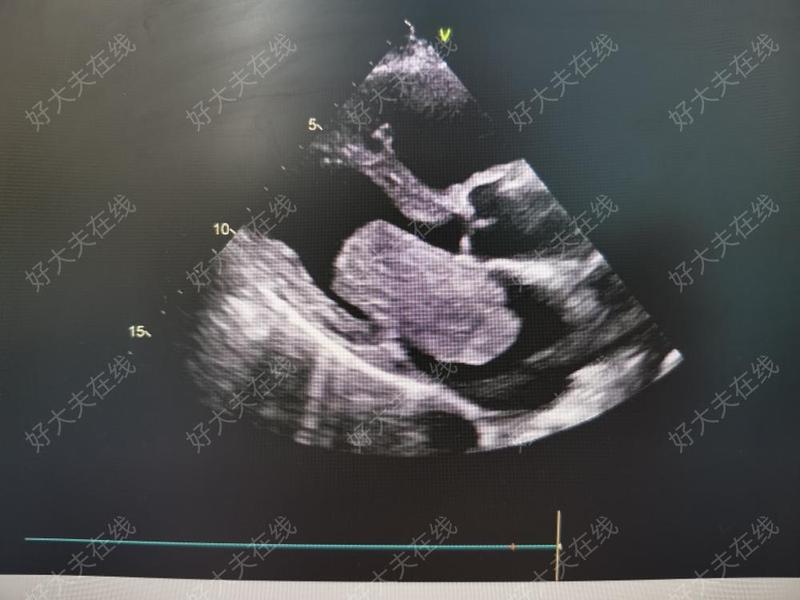

左房粘液瘤

治療前左心房巨大粘液瘤,造成二尖瓣重度反流、三尖瓣重度反流,術前心功能衰竭,納差、乏力,消瘦1年余治療后治療后0天手術摘除7cm左房粘液瘤后,二尖瓣反流消失。術后當天拔除氣管插管,術后第二天轉出普通病房,患者精神、胃口佳

心臟腫瘤為少見病,心臟原發(fā)性腫瘤更少見,后者約75%為良性,其中最常見的為黏液瘤,心臟黏液瘤可發(fā)生在各房室腔,以左房最常見。粘液瘤有蒂,較大而有蒂的粘液瘤可造成血流受阻,可造成暈厥或猝死,瘤體通常呈半透明膠凍狀,表面可見大小不等的結節(jié),質地較軟,易脫落。脫落的瘤體可引起體循環(huán)動脈的栓塞,如腦動脈、腹主動脈、上下肢動脈等。瘤體舒張期可隨血流進入二尖瓣口,造成二尖瓣狹窄,影響左房血液的回流,左房增大;收縮期瘤體又回到左房內,呈往返運動。因可導致較嚴重后果,黏液瘤診斷后應及時手術切除。超聲心動圖是診斷左心房粘液瘤的首選檢查方法。上面是我們組2022年上半年切除的左房粘液瘤照片。粘液瘤是臨床上最常見的心臟腫瘤,大部分是良性,小部分會復發(fā)。所以術后仍需定期復查心臟彩超。心臟惡性腫瘤也會遇到,無法完整切除,預后不佳。